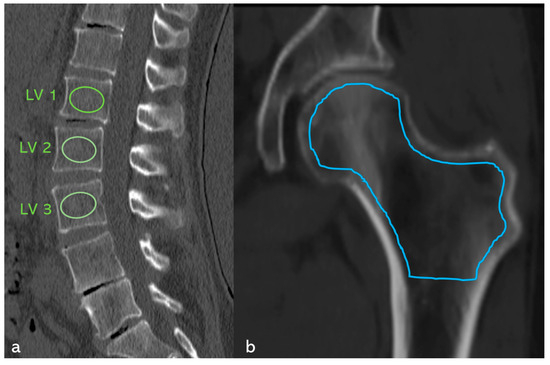

Diagnostic Value of Opportunistic CT-Based Bone Density Assessment in Patients with and Without Sacral Insufficiency Fractures

Background/Objectives: This retrospective observational cohort examined whether opportunistic CT-derived Hounsfield units (HU) of the lumbar spine and proximal femur together with serum 25-OH-vitamin D can predict sacral insufficiency fractures (SIF) and osteoporosis. No interventional procedures were performed. Methods: Consecutive suspected SIF cases over [...] Read more.

Background/Objectives: This retrospective observational cohort examined whether opportunistic CT-derived Hounsfield units (HU) of the lumbar spine and proximal femur together with serum 25-OH-vitamin D can predict sacral insufficiency fractures (SIF) and osteoporosis. No interventional procedures were performed. Methods: Consecutive suspected SIF cases over 3 years (n = 253) were assigned to SIF (n = 98) or controls without SIF or spine/hip fractures (n = 155). HU were measured using ellipsoidal ROIs at L1–L3 and an irregular area ROI across the entire proximal femoral cancellous bone; vitamin D was quantified; ROC analyses assessed discrimination. HU cut-points were referenced via HU-to-QCT/CTXA conversions. Results: SIF patients had markedly lower HU than controls (lumbar 44.84 vs. 105.66 HU; femoral 47.0 vs. 148.0 HU). Diagnostic performance was excellent (AUC 0.98 for SIF discrimination using lumbar HU; AUC 0.98 for osteoporosis prediction using femoral HU). Vitamin D deficiency (<20 ng/mL) was highly prevalent (92.9%) with lower means in SIF (3.72 vs. 8.24 ng/mL). Within SIF, patients with hip fracture had femoral HU ≈ 14.2 vs. 70.6 without hip fracture; effect sizes were very large. Conclusions: Opportunistic HU assessment from routine CT provides a rapid, reproducible surrogate of bone density that distinguishes SIF with near-perfect accuracy and identifies osteoporosis. HU thresholds around ~96–98 are consistent with osteoporotic ranges and can be implemented to trigger metabolic evaluation and early osteoanabolic therapy where appropriate. Full article

Show Figures

Figure 1